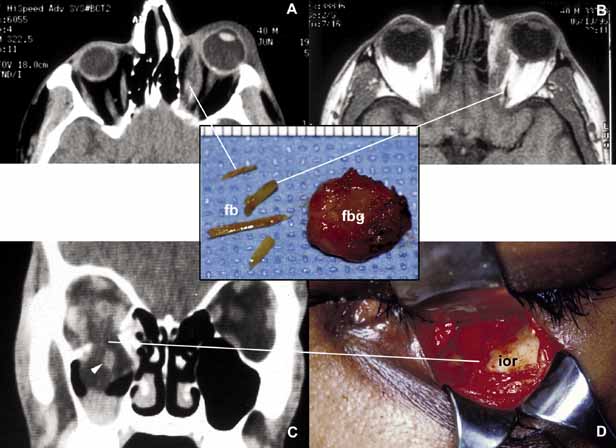

Orbital injuries result from the absorption of kinetic energy that occurs whenever the orbital tissues contact an object moving at a different speed.25 The orbital rim is capable of absorbing a considerable amount of kinetic energy without being fractured. Yet, a variety of impact forces striking the orbit may result in fractures in different areas.26 The absorption of the kinetic energy by an orbital bone may lead to contusion and/or laceration of the skin and superficial soft tissues, local deformation of the adjacent structures, globe, orbital soft tissues and bones and increases pressure in the orbital cavity. A common end result of an orbital impact is the fracture of the floor and/or the medial wall (lamina papyracea)27 (Fig. 3). Fractures of other orbital bones occur less often. Foreign bodies may be introduced into the orbit at the time of injury and may cause secondary problems depending on the nature and the location of the foreign body.28 Some foreign bodies such as copper may cause tissue necrosis and degeneration (chalcosis), and others particularly organic matter, may carry organisms such as bacteria and fungi into the orbital tissues and cause secondary infections29 (Fig. 3). Once the fracture of an orbital bone occurs, it may produce sharp edges to lacerate adjacent soft tissue structures including the globe, optic nerve, other nerves, muscles, and vessels.30 Depending on the damage of the particular tissue, functional deficit results.

Fig. 3 Orbital trauma. Axial CT scan (A) and T1-weighted MRI (B) show multiple organic foreign bodies (fb) within the left medial rectus muscle and posterior orbit. The round tissue depicted in the inset was removed at the time of surgery; histopathologically it proved to be a foreign body granuloma (fbg). A coronal CT scan (C) and the intraoperative photograph (D) depict a large, inferior orbital rim (ior) fracture. The right inferior rectus muscle that was prolapsed into the maxillary sinus is highlighted with an arrowhead (C). (A and B are the courtesy of J. Christopher Fleming, MD of Memphis, TN)

Orbital cellulitis may also be caused by different types of foreign bodies including organic and nonorganic matter and nonautogenous surgical implants.28 Inorganic foreign materials, such as metal and glass, are usually well-tolerated and do not cause infection unless they significantly distort the orbital anatomy with exposure to periorbital sinuses and nasal cavity. Organic foreign bodies such as wood, vegetable fibers, etc., however, trigger significant foreign body reaction and sometimes suppurative inflammation.These should be documented by CT and/or MRI and surgically removed29 (Fig. 3). Today many nonautogenous materials are used in ocular and orbital reconstruction, including porous implants, mesh materials, polymeric silicone plates, sponges for scleral buckling procedures and reservoirs of drainage valves for glaucoma. Implants and repair blocks made of porous materials may lead to acute infection when they erode through sinus or conjunctival epithelium. Whenever there is a foreign body, noncaseating granulomatous reaction with multinucleated giant cells is identified, adjacent to the foreign material; secondary acute inflammation may be superimposed. In penetrating injuries the nature of the foreign body is an important factor.